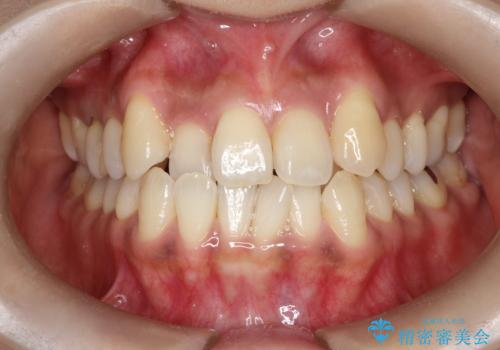

[セラミック治療] 前歯の審美治療に伴う矯正治療